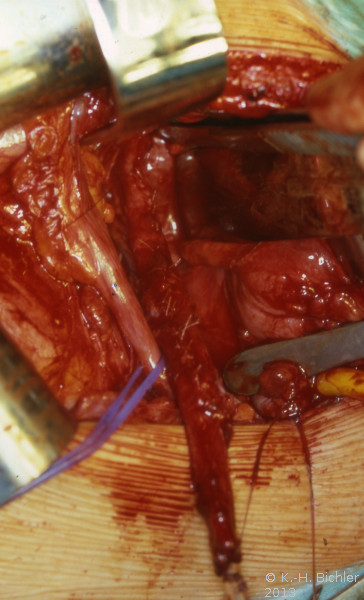

Bei dem 16 Jahre alten Jungen wurde aufgrund der ausgedehnten Ureterozele mit sekundärem partiellem Megaureter insbesondere Dilatation des Harnleiters und länger dauernden rezidivierenden Harnwegsinfekten eine offen Ureterozelenabtragung und Ureterreimplantation durchgeführt (Abbildung 7).